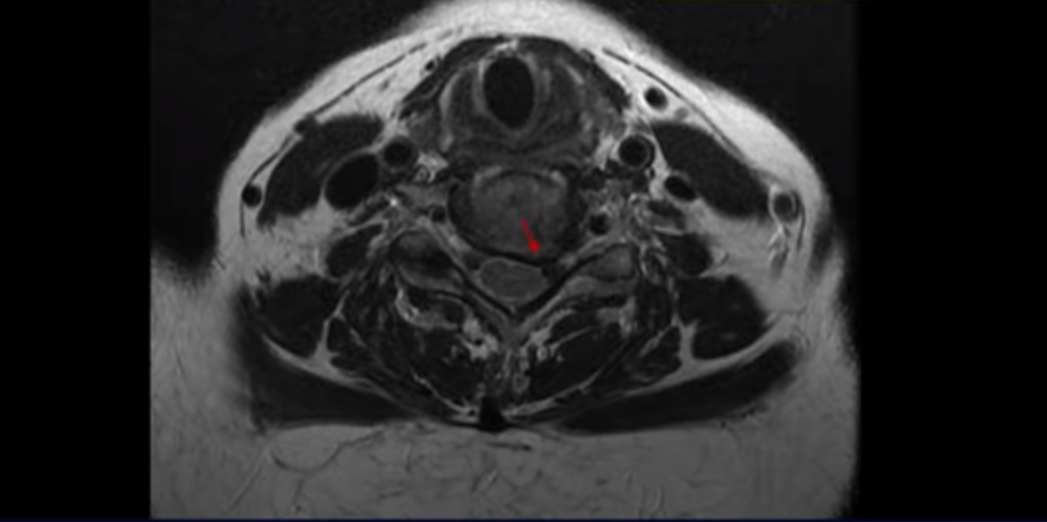

우선 이분 MRI를 보면 목디스크 6번 7번에 오른쪽으로 디스크가 터져서 밀려 나와 있습니다. 이 문제가 오른쪽 팔 통증과 견갑골 통증을 일으키는 걸로 보입니다.

4번 5번과 5번 6번에서도 신경길이 좁아져있지만 왼쪽 방향이라 오른쪽 방사통은 이 6번 7번 디스크 때문으로 보입니다.